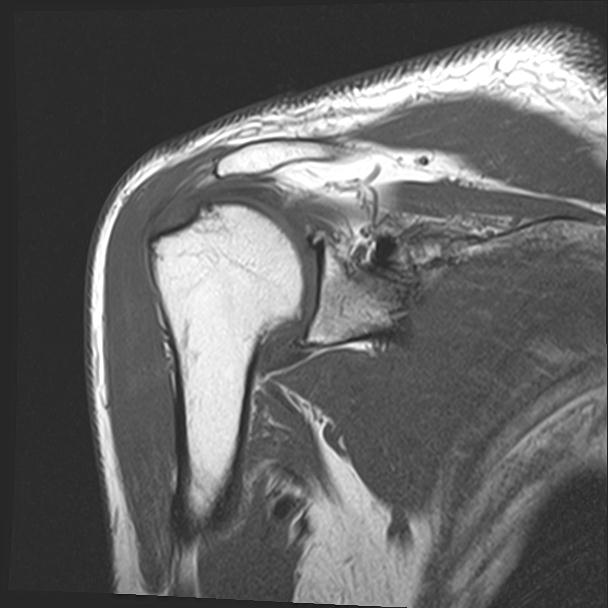

60058 3/9 11/4 右肩 2R+MRI 73歳男性 肩腱板損傷